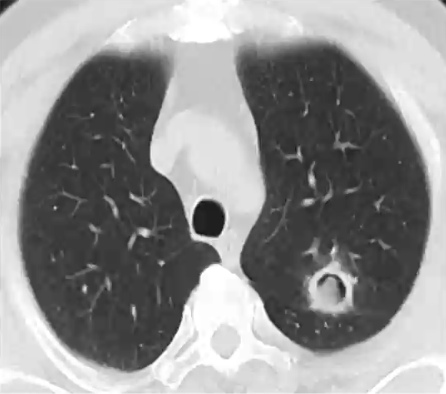

空气新月征(air-crescent sign,ACS)

❖ 定义:病灶内中央坏死结构及外周出血的肺实质之间形成了新月形的裂隙

❖ 属真菌感染晚期表现,常见于血液恶性肿瘤患者的粒缺恢复阶段

❖ 经治疗或患者免疫功能部分恢复后,真菌所致梗死灶中心收缩而外周的坏死组织被白细胞吞噬吸收

❖ 除了侵袭性真菌感染外,还可见于:细菌感染,形成空洞的肿瘤,血管炎等